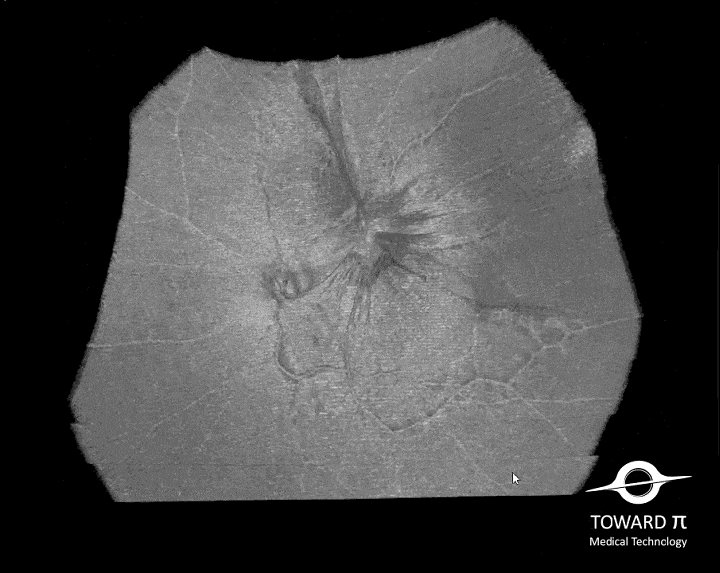

- Wide-field OCTA

- Choroid OCTA with Quantification Parameters